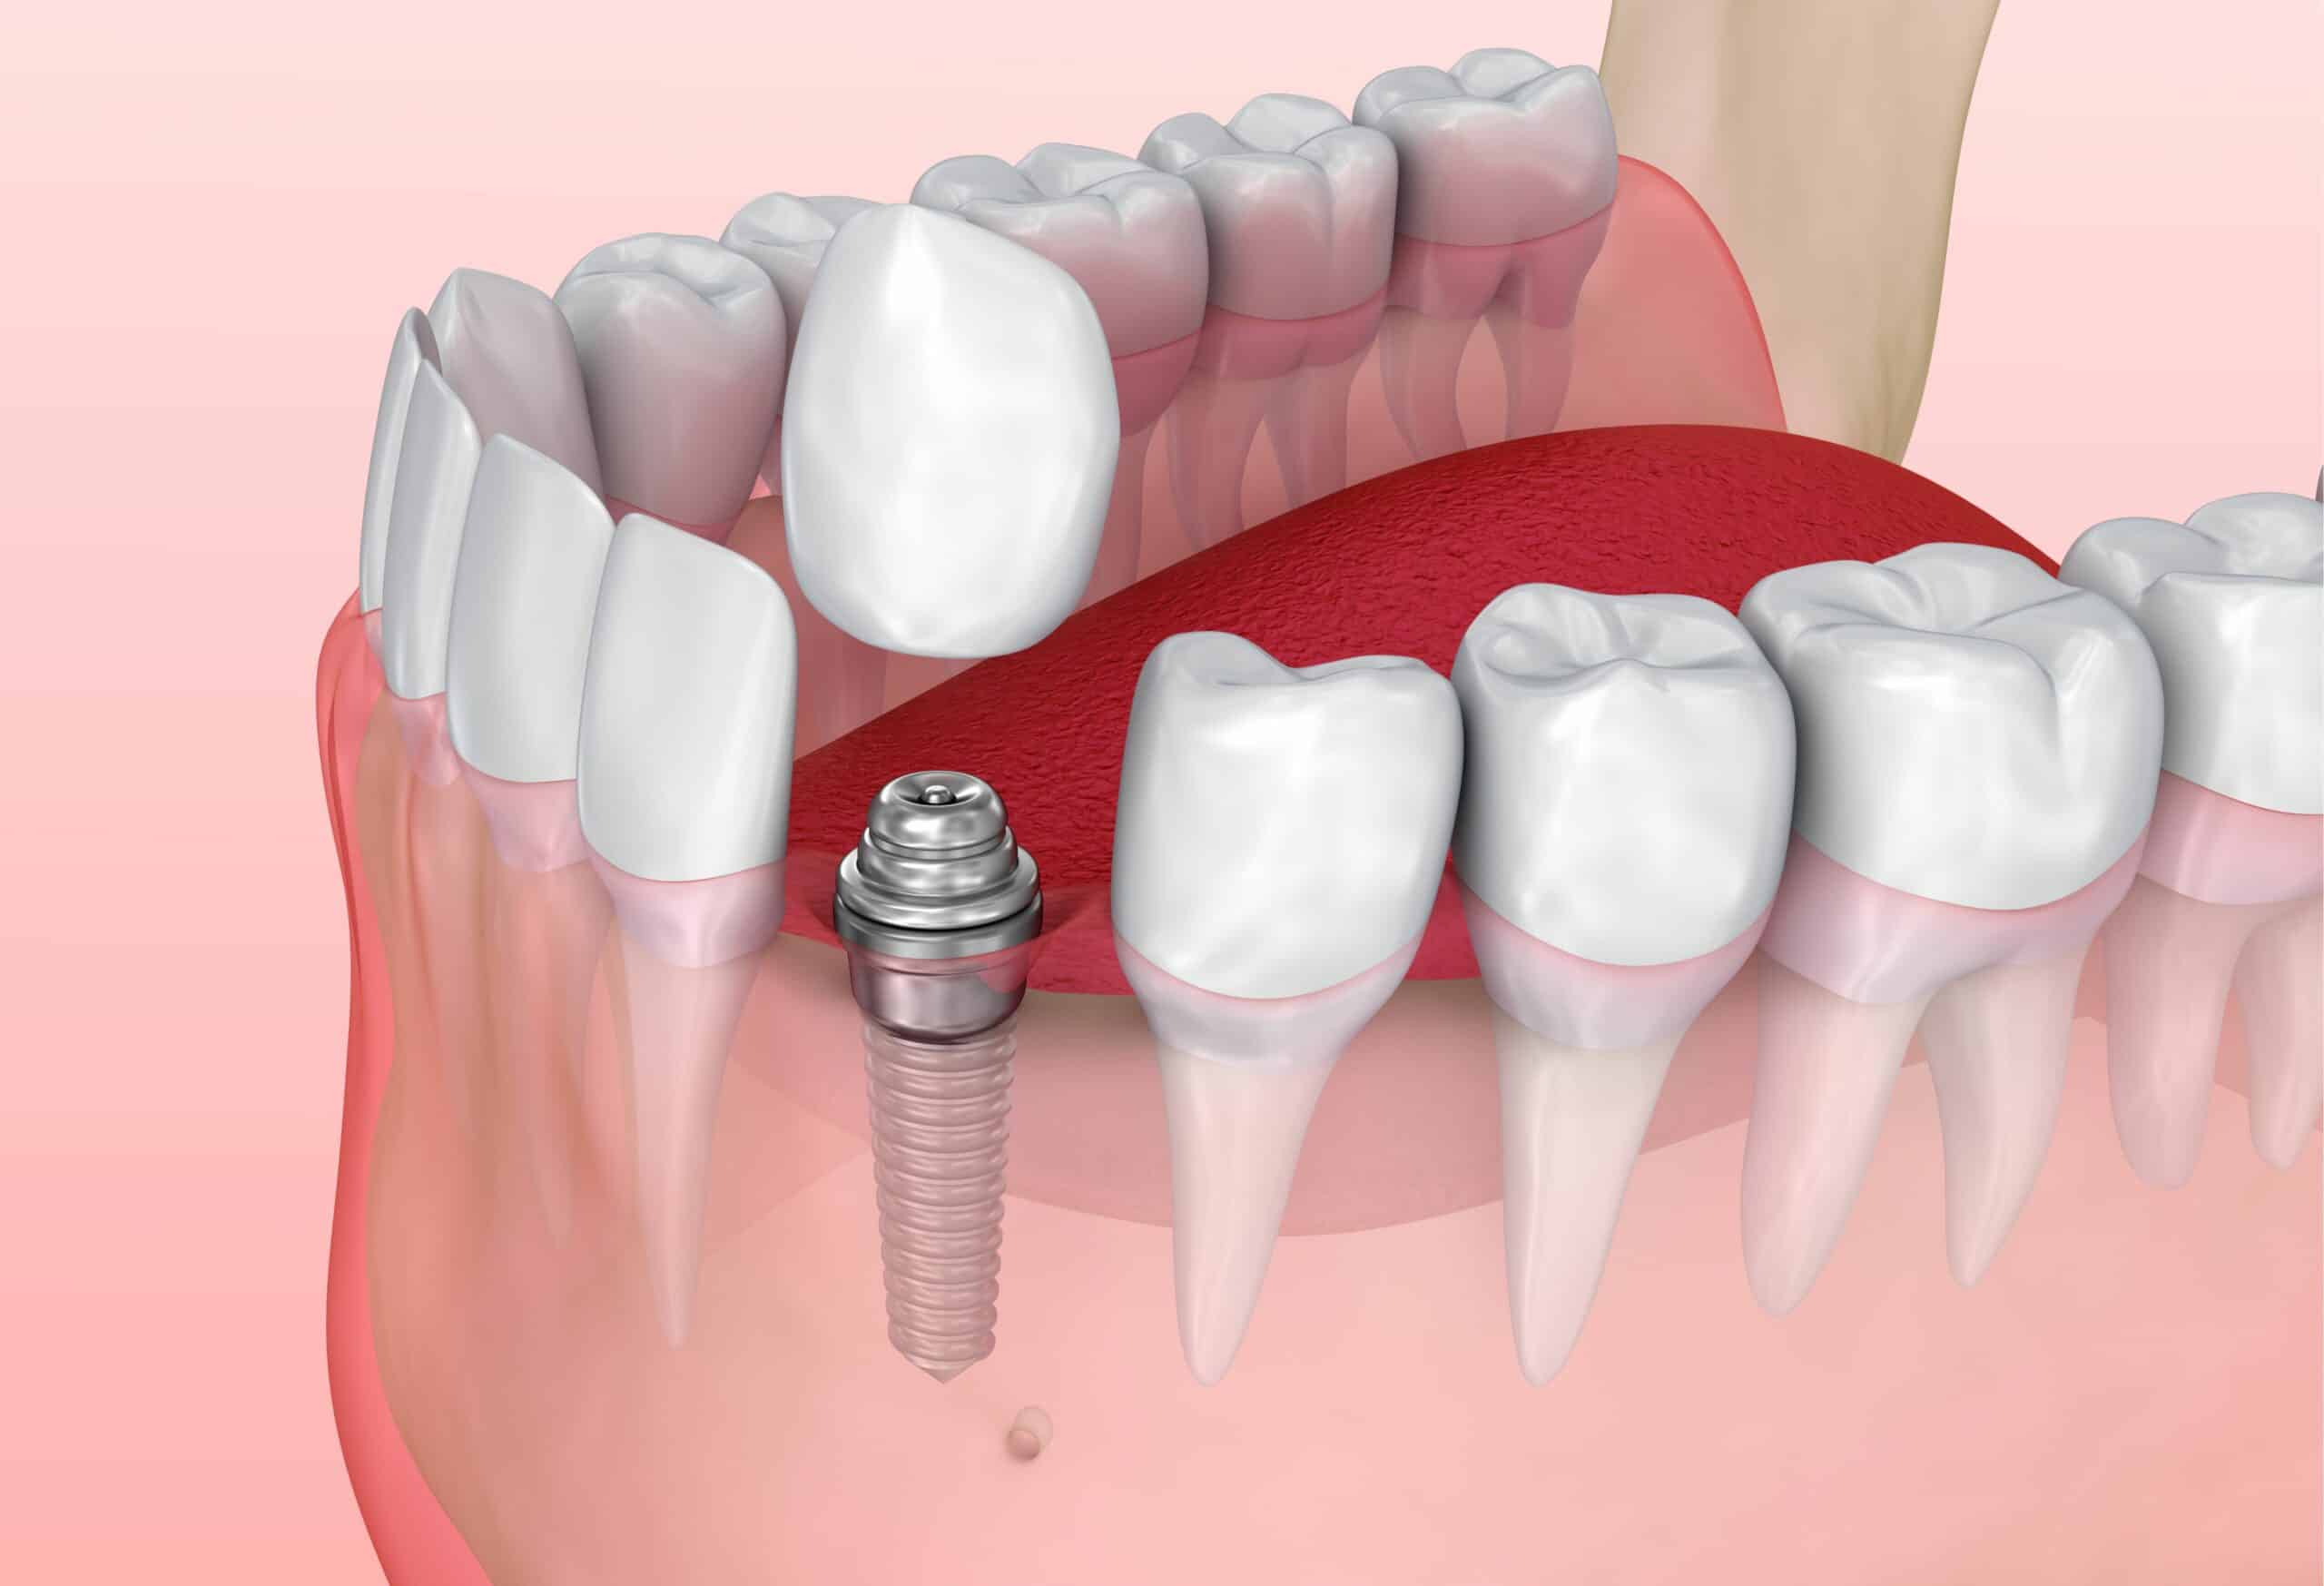

Современные коронки на зубные импланты: виды и фото-примеры